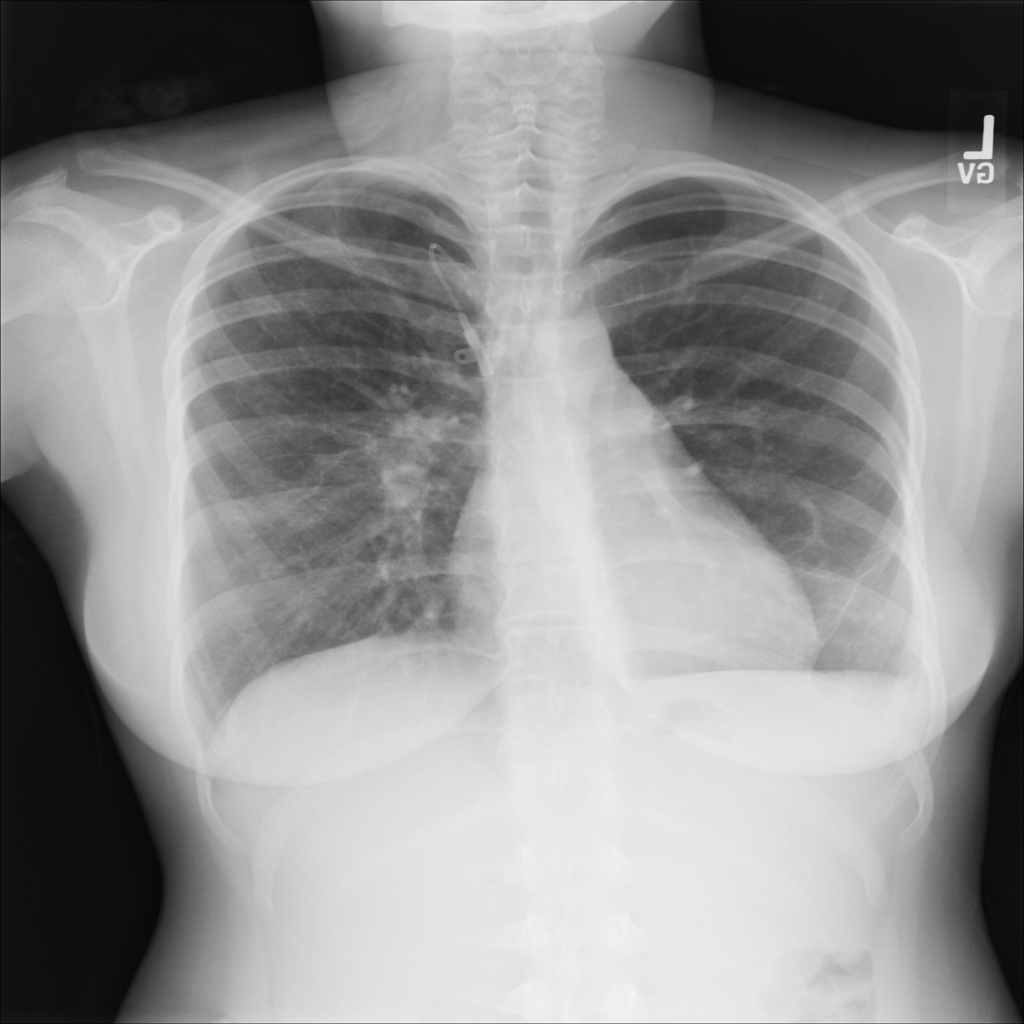

PAT-E960 · IMG-002Fibrosis

PAT-E960 · IMG-002

PA